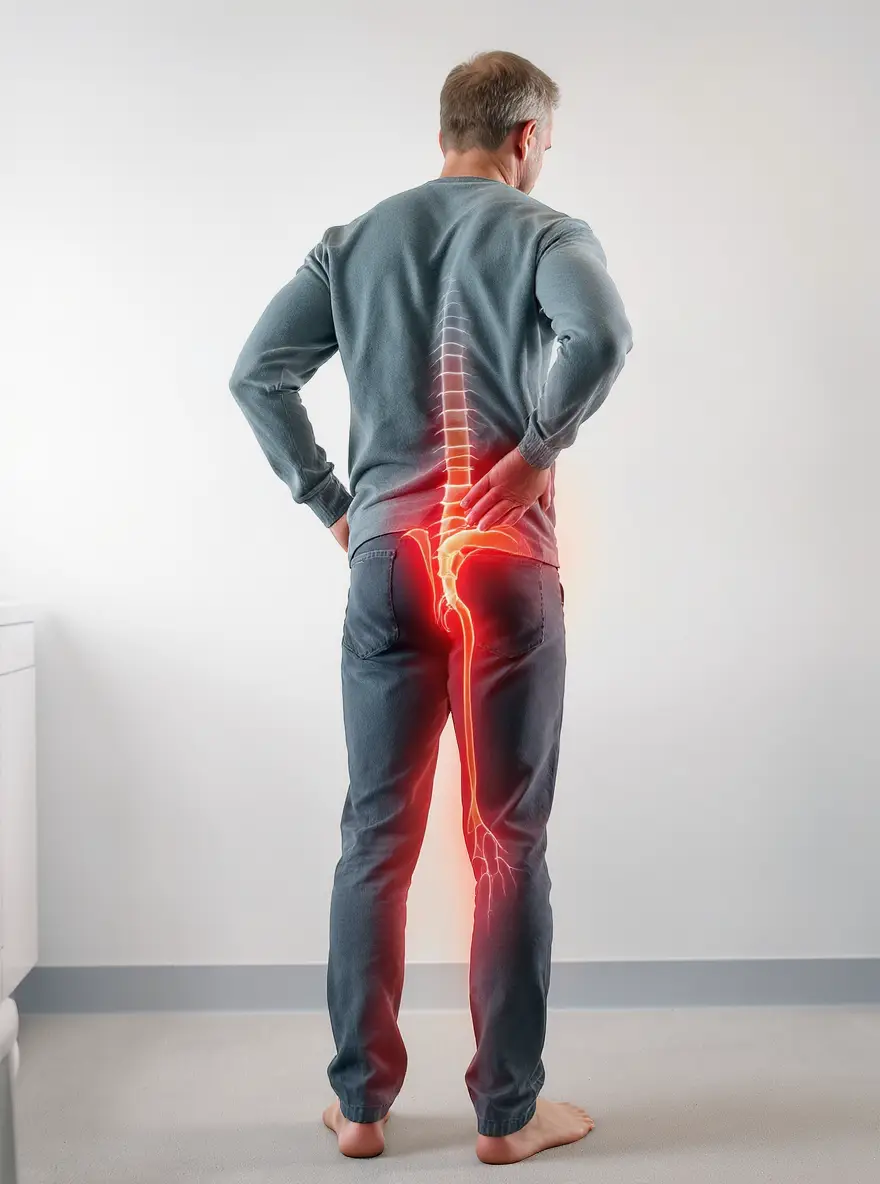

Beaucoup de douleurs chroniques concernent des tissus riches en fibroblastes — tendons, ligaments, fascias, enthèses et périoste. Ces cellules répondent à la contrainte via la mécano-transduction : le signal mécanique devient réponse biologique (organisation du collagène, remodelage de la matrice, modulation de l’inflammation), susceptible d’améliorer douleur et fonction. L’enthèse désorganisée entretient souvent les douleurs d’insertion.